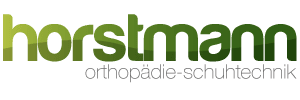

Fehlen noch Sesambeine, Fettpolster und die Faszien.

Sesambeine sind kleine Knochen. Durch ihre Position sorgen sie dafür, dass Bewegungen maximal effektiv ausgeführt werden können. Am Fuß findet man zwei Sesambeine an der Großzehe. Ein Fettpolster unter der Haut unserer Fußsohle wirkt wie ein Stoßdämpfer und gibt zusätzliche Stabilität im Fuß. Ebenfalls geben Faszien (sogenannten Muskelhäute) zusätzliche Stabilität.

Die Sesambeine sind am Großzehengelenk in den Muskel eingebettet und sorgen dafür, dass eine Sehne im richtigen Winkel verläuft. Außerdem haben sie Kontakt zum Großzehengelenk, dadurch wird der Winkel für die Bewegung vergrößert. Das ist wichtig für eine effiziente Umsetzung der Kraft, die für eine Bewegung aufgebracht wird (Biomechanik).